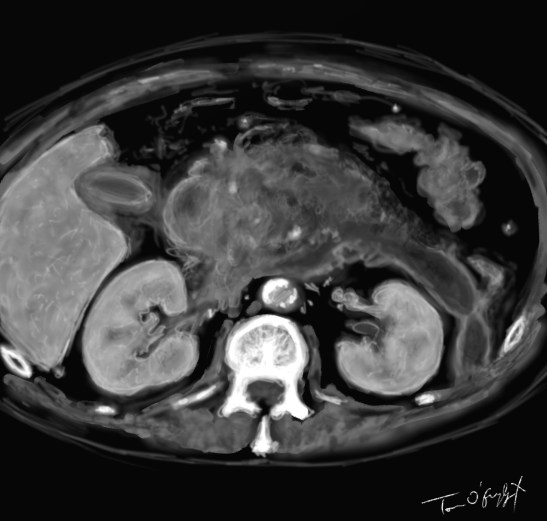

scanner de pancréatite aiguë nécrosante stade E avec importante réaction oedémateuse et coulée de nécrose

Le score scanographique de Balthazar classe en 5 stades l’évolutivité :

L’évaluation de la taille de nécrose (0 : défaut de rehaussement du parenchyme, < 30 %, 30-50 %, > 50 %) compte aussi.